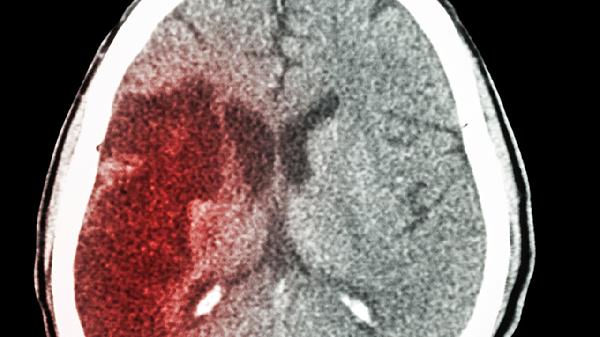

3、脑血管病后遗症

脑血栓、脑出血等脑血管疾病恢复期服用该药物,有助于减轻言语障碍、肢体活动不利等后遗症。其作用机制包括促进受损神经纤维再生和突触重建。临床应用时常与康复训练联用,恢复期为3-6个月效果较显著。